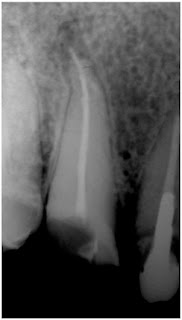

Ahora bien, producida la sobreobturación ¿ella per se puede ser la causa del fracaso del tratamiento endodóntico?. Para contestar esta pregunta necesitamos diferenciar la sobreobturación de la sobreextensión. Se entiende por sobreobturación, la extravasación de una pequeña cantidad de sellador o gutapercha hacia la zona perirradicular (apical o lateral) siempre y cuando se haya logrado con la obturación un correcto sellado tridimensional del conducto radicular (Fig.1). En tanto, se designa como sobreextensión, la extravasación de sellador o gutapercha acompañando una deficiente obturación endodóntica (Fig.2).

Fig.1 Imagen radiográfica de un caso con sobreobturación periapical (flecha negra) y lateral (flecha blanca)